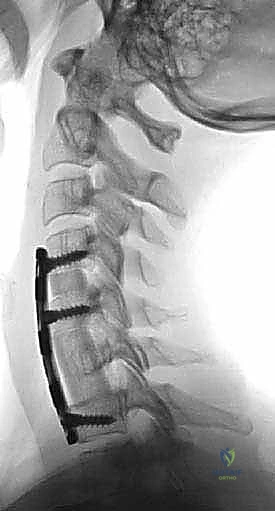

الخطوة 5: التثبيت بالشريحة والمسامير

لضمان ثبات الدعامة ومنع حركتها حتى يكتمل الالتحام العظمي (الذي يستغرق عدة أشهر)، يتم تثبيت شريحة معدنية من التيتانيوم على الجزء الأمامي من الفقرات السليمة (التي تقع أعلى وأسفل الدعامة) باستخدام مسامير طبية خاصة.

* الشفاء التام والاندماج العظمي الكامل قد يستغرق من 3 إلى 6 أشهر، ولكن التحسن في الأعراض العصبية (مثل التنميل وضعف الأطراف) غالباً ما يُلاحظ في الأسابيع الأولى.